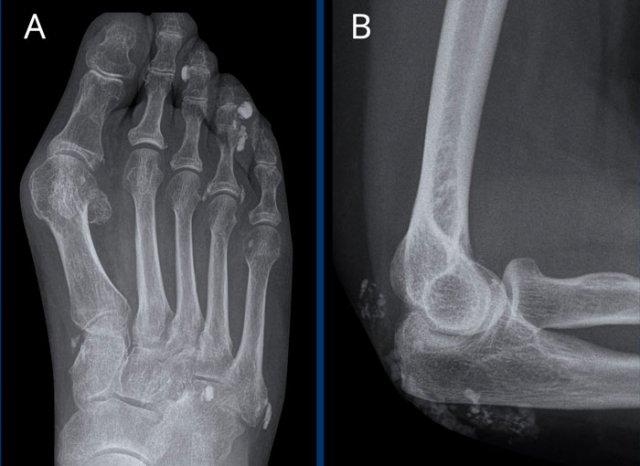

Biến dạng bút chì trong cốc

A. Biến dạng bút chì trong cốc tại ngón chân thứ 1 và thứ 5.

B. Tiêu xương đầu ngón (acro-osteolysis) với tiêu xương chỏm đốt ngón xa của ngón 2-4 và 5.

Có bào mòn xương tại khớp bàn ngón chân (MTP) 2 và 3.

Giai đoạn muộn của Gout

Các thay đổi X-quang đặc trưng trong giai đoạn mạn tính của bệnh gout.

Điển hình là các bào mòn lệch tâm dạng “đục lỗ” bờ rõ nét với viền xơ cứng, phân bố ở rìa khớp và cạnh khớp.

Các bào mòn này có bờ nhô ra được gọi là bào mòn dạng “chuột cắn” (rat bite erosions).

Khe khớp được bảo tồn.

Sưng mô mềm tăng tỷ trọng quanh khớp do hạt tophi là hậu quả của lắng đọng tinh thể (dấu hiệu đặc trưng bệnh lý).

Các hạt này nằm trong các cấu trúc dây chằng quanh khớp.

Tổn thương điển hình tại khớp MTP1 với bào mòn dạng “đục lỗ”.

Sưng mô mềm biểu hiện cho hạt tophi.

Trật khớp không phải là dấu hiệu thường gặp trong gout, nhưng trong trường hợp này là hậu quả của các bào mòn và tổn thương dây chằng.

Tỷ trọng mô mềm

Sưng mô mềm tăng tỷ trọng điển hình bao quanh khớp MTP1 hai bên.

Bào mòn cạnh khớp ở mặt trong của đầu xương bàn chân (MT) phía xa, có viền xơ cứng.

Tổn thương rõ nhất ở bên phải (mũi tên).